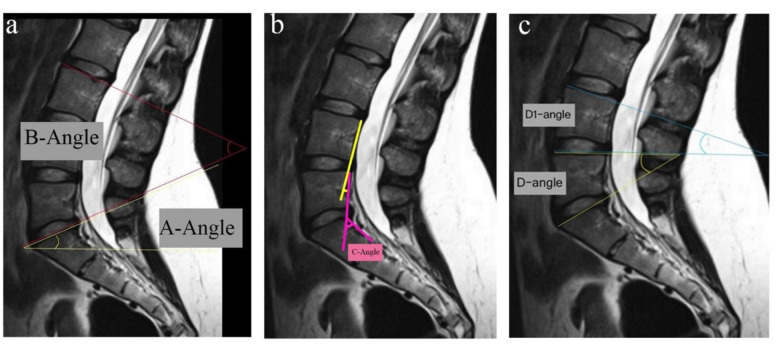

Methods: We recruited 220 patients referring to our hospital for routine lumbar MRI during 2020-2021. All the participants were subject to routine sagittal lumbar MRI, whole spine localizer scan, and coronal MRI to numerate lumbar vertebrae. Five vertebral angles (A, B, C, D, and delta) and dehydration in L4-L5 and L5-S1 discs were assessed in sagittal MRI scans. Data were analyzed using SPSS 26.

Results: Out of 220 participants (mean age: 44.29 ± 14.14 years), 36 (16.36%) were diagnosed with LSTV. Among those diagnosed with LSTV, L5-S1 dehydration was less frequently observed compared to other participants (P < 0.001). Multivariate regression showed that dehydrated L4-L5 disc, non-dehydrated L5-S1 disc, increased A-angle, and decreased D-angle can independently predict LSTV. The median A-angle was significantly larger in LSTV patients than in non-LSTV participants (P = 0.038), while the medians of C-angle, D-angle, and delta-angle were significantly smaller in the LSTV group (P < 0.05). A C-angle ≤ 35.5˚ could diagnose LSTV with sensitivity and specificity of 72.2% and 57.6%, respectively. A delta angle ≤ 8.5˚ could diagnose type 2 LSTV with 92.3% sensitivity and 87.9% specificity.

Conclusion: Measuring lumbosacral vertebral angles, especially delta-angle, in routine sagittal MRI can potentially alert physicians of a likely LSTV diagnosis.